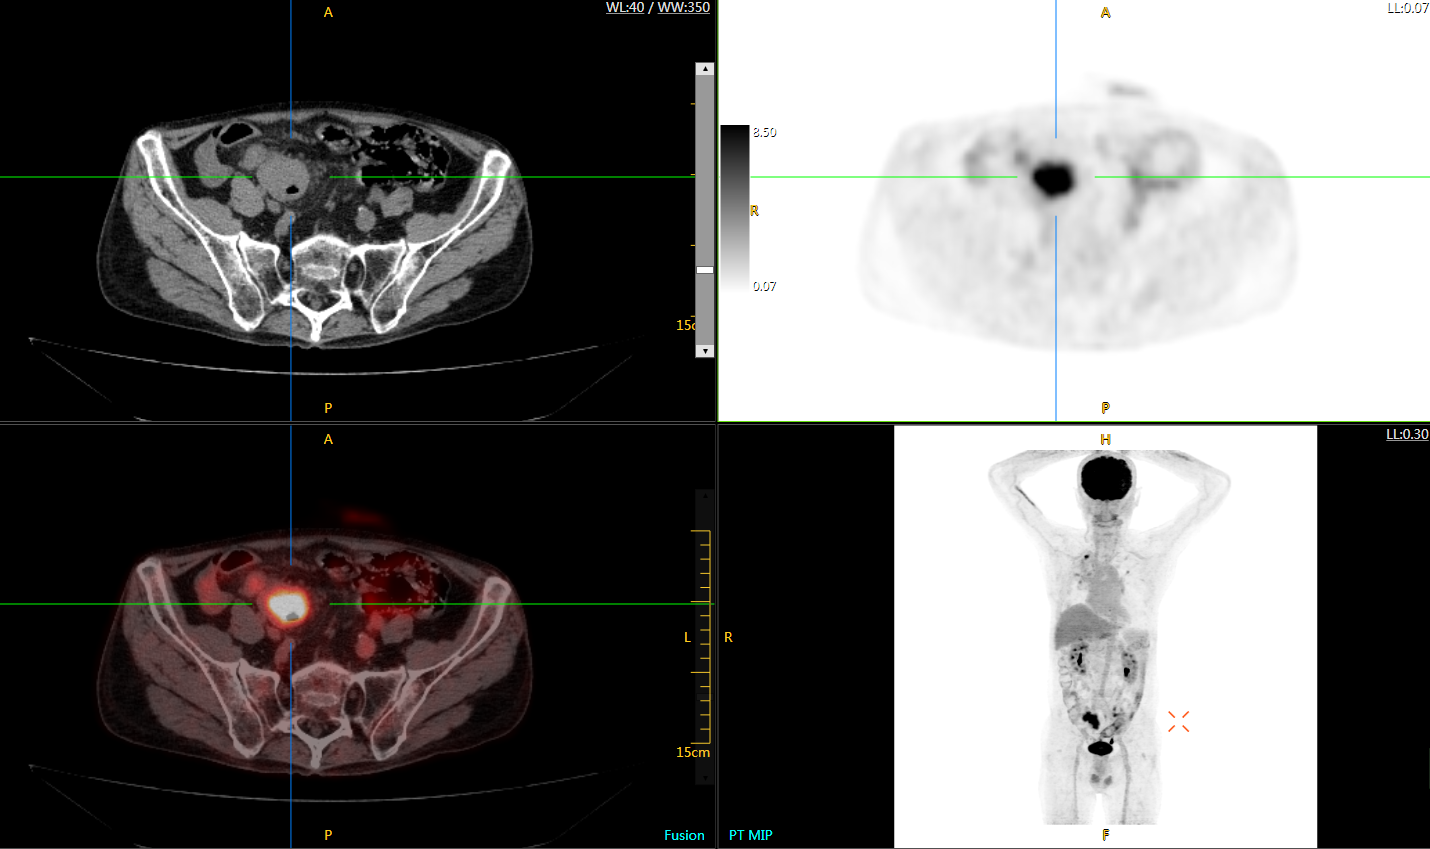

肺癌轉(zhuǎn)移及復發(fā)

患者男性,66歲,七年前發(fā)現(xiàn)右肺肺癌,其間手術兩次,共切除兩個肺葉,復查;

診斷意見,回腸轉(zhuǎn)移,右肺殘留部復發(fā)